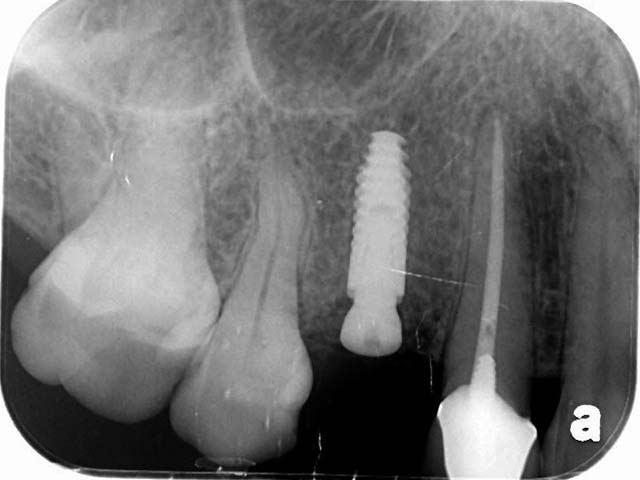

王小姐右上有一顆根管治療後的牙齒,不幸斷裂,經由電腦斷層評估,我們使用新技術,即拔即種,拔除右上第一小臼齒同時植入植體,降低患者手術疼痛感,與節省時間,經由四個月的等待牙齒終於裝置完成,回復正常咀嚼功能,與良好的美觀。